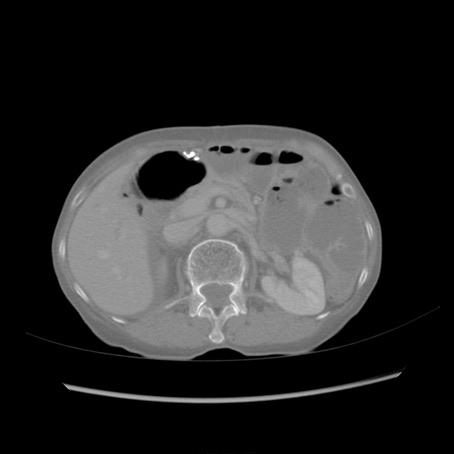

冠状断像

症例25(横断像)

【症例】80歳代女性

【主訴】胸のつかえ感

【現病歴】約9時間前に食後から胸のつかえた感じあり、嘔吐あり、来院。

【既往歴】胃癌(全摘)、胆摘、虫垂炎

【身体所見】心窩部に圧痛あり、反跳痛なし。

【データ】WBC 5700、CRP 0.05